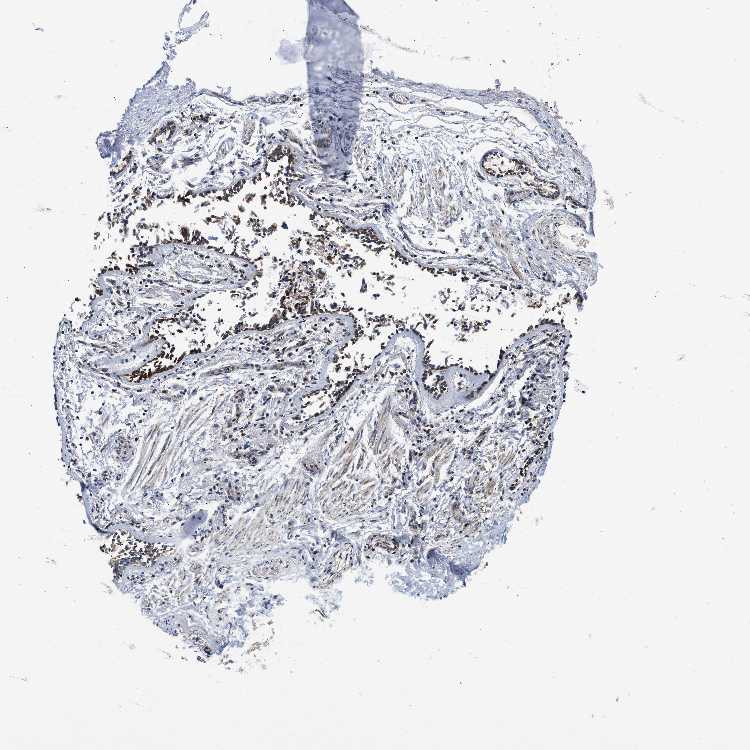

ADIPOSE TISSUE - Antibody stainingi

Antibody staining in the annotated cell types in the current human tissue is reported as not detected, low, medium, or high, based on conventional immunohistochemistry profiling in selected tissues. This score is based on the combination of the staining intensity and fraction of stained cells.

Each image is clickable and will lead to virtual microscopy that enables deeper exploration of all samples and also displays staining intensity scores, fraction scores and subcellular localization as well as patient and tissue information for each sample.

Antibody HPA018483Antibody HPA019081Antibody HPA021152

Adipocytes Not detectedNot detectedMedium